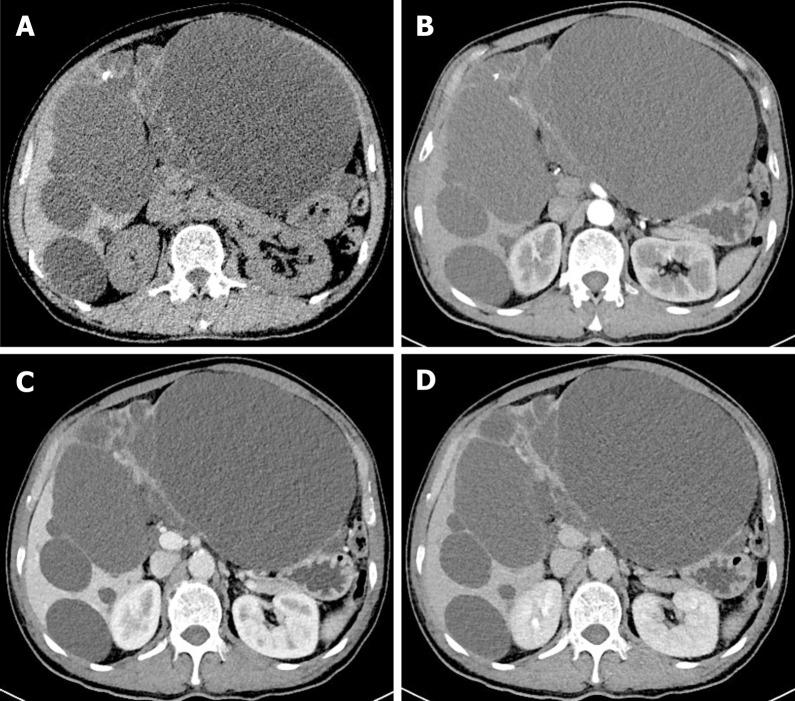

Intrahepatic biliary cystadenoma: A case report.

A 58-year-old man with irregular abdominal discomfort came to our clinic and was found to have a distended abdomen during physical examination. Computed tomography and magnetic resonance imaging both showed a huge cystic mass in the liver. The patient underwent left hepatic lobectomy, cholecystectomy, and liver cyst fenestration, and most of the masses had decreased in size as of the 6-mo follow-up. The pathological diagnosis was consistent with BCA, and no recurrence was detected after the surgery. BCA occurred mainly in middle-aged women. To the best of our knowledge, this patient is the 11th male case of BCA reported in the literature.